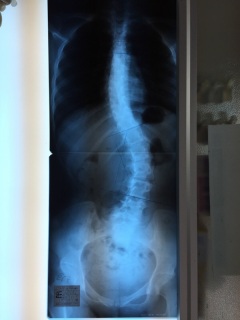

側弯

現状維持かなぁ

上が曲がってきちゃった…